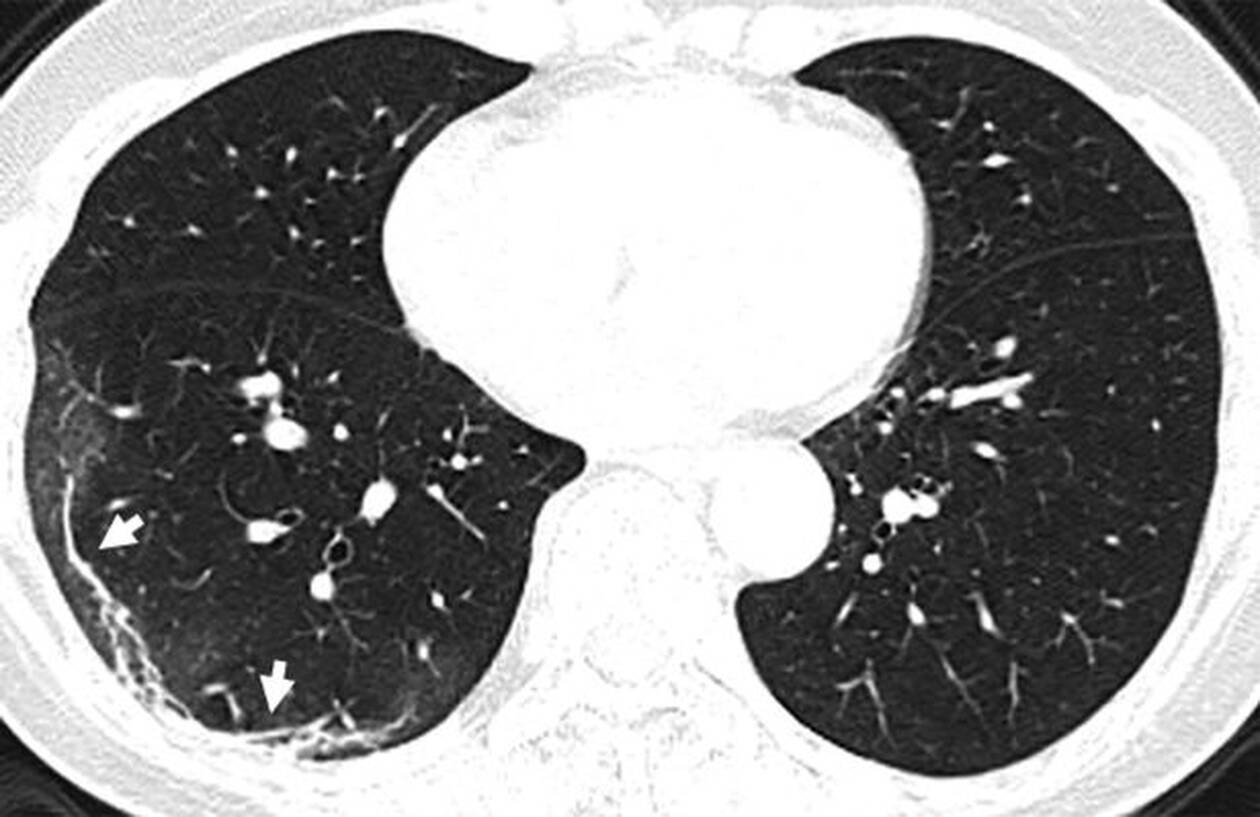

Η πανδημία του κοροναϊού covid-19 συνεχίζει να καλπάζει σε όλο τον πλανήτη, με τους γιατρούς να παρακολουθούν την έξαρσή του. Περισσότεροι από 4.000 άνθρωποι έχουν χάσει τις ζωές τους από τις επιπλοκές του ιού, ο οποίος προκαλεί σοβαρό πρόβλημα στους πνεύμονες των ασθενών. Στην δημοσιότητα δόθηκαν από την Ραδιολογική Κοινότητα της Βορείου Αμερικής ακτινογραφία πνευμόνων ασθενών, οι οποίοι είχαν προσβληθεί από τον κοροναϊό, οι οποίες προκαλούν ανατριχίλα.

Οι ασθενείς που έχουν νοσήσει μέχρι στιγμής έχουν περιγράψει την εμπειρία τους ως μια «τρομακτική προσπάθεια για να αναπνεύσουν». Στις ακτινογραφίες διακρίνονται κάποια άσπρα σημάδια, χαμηλά στους πνεύμονες. Περιγράφονται ως υγρό στις κυψέλες του πνεύμονα. Να σημειώσουμε πως οι ακτινογραφίες αυτές που δόθηκαν στην δημοσιότητα είναι από ασθενείς από την Κίνα που νόσησαν με επιπλοκές, οπότε δεν έχουν καμία σχέση με το αν νοσήσει κάποιος ο οποίος δεν αντιμετωπίζει προβλήματα υγείας.